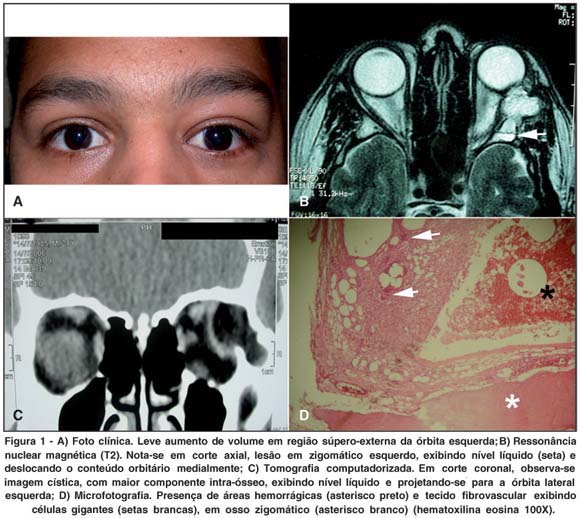

Ao exame apresentava visão igual a 1,0 em ambos os olhos. Havia exoftalmo de 3 milímetros à esquerda, além de leve deslocamento inferior e medial do globo ocular (Figura 1A). Notava-se abaulamento da parede lateral da órbita à esquerda, sem massa palpável. Não havia outros achados anormais ao exame. Trazia tomografia computadorizada (TC) e ressonância nuclear magnética (RNM) das órbitas, que revelavam lesão hipodensa, exibindo nível líquido, ocupando parte dos ossos zigomático, frontal e esfenóide à esquerda, com projeção para cavidade orbitária, deslocando medialmente as estruturas orbitárias e causando retificação da esclera lateralmente (Figura 1B).

O estudo anátomo-patológico revelou tecido ósseo com presença de múltiplos espaços císticos, preenchidos por hemácias, sem cobertura endotelial. Separando os cistos, existiam septos contendo fibroblastos alongados e células gigantes multinucleadas (Figura 1D). O diagnóstico final foi de COA orbitário. O paciente evoluiu bem, não apresentando sinais de recidiva no controle radiológico após seis meses de acompanhamento.